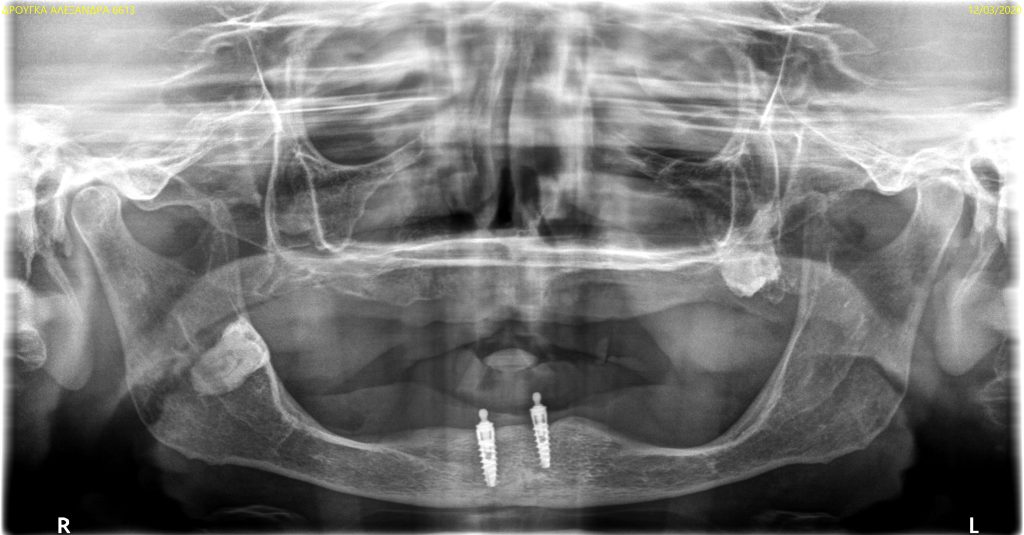

The use of CDP (Complete Digital Patient) as a basis for planning in a case of complete implant rehabilitation with a full arch in zirconia – ceramicised

Case study carried out with Athena Smile Pelekanos (GR ) : dott . Stavros Pelekanos